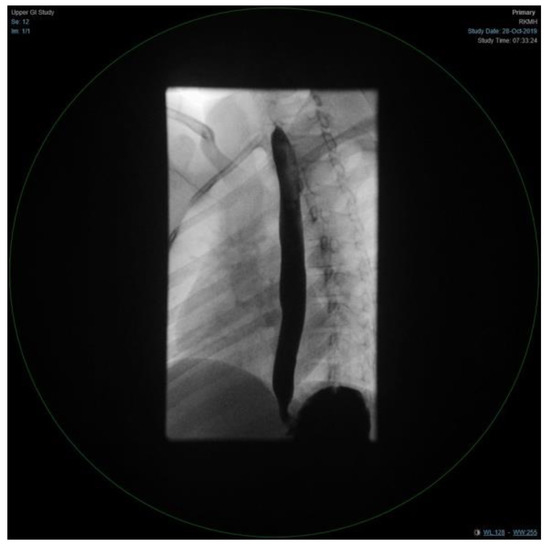

The patient condition necessitated a multidisciplinary approach, involving several sub-specialties, and requiring multiple laboratory workup and diagnostic procedures. Her initial workup, constituting of full blood count, electrolyte, and blood gases, were all within normal limits (Table 1). Similar to the findings of her primary treating hospital, her chest x-ray showed patchy infiltrates, primarily over the lower zones (Figure 2). It was consistent with the results of the computed tomography (CT) scans of the chest, which illustrated the presence of bronchiectasis involving the lower zones (Figure 3). Moreover, she underwent bronchoscopy and bronchoalveolar lavage a few days after starting antibiotics. Bronchoscopy findings showed mild erythematous change of the airway with no purulent secretions distally, while the lavage showed no growth of any bacterial organisms, including acid-fast bacilli. Although endoscopy failed to demonstrate any anatomical abnormality, severe reflux was noted on the barium swallow test (Figure 4). To assess the copious nasal discharge, the patient underwent a CT sinus scan and nasopharyngeal scope, confirming the diagnosis of infectious ethmoid and maxillary sinusitis on a background of allergic rhinitis. Immunological workup was carried out to rule out any primary immunodeficiency conditions, including lymphocyte subsets, immunoglobulin subclasses, tetanus, and diphtheria antibodies. All tests, except the lymphocyte subsets, demonstrated a normal result (Table 1). The standard spirometry showed mild partially reversible obstructive airflow limitation with FVC 75%, FEV1 of 65%, FEV1/FVC 71% and mid-expiratory airflow of 45% with 20% improvement post-challenge with bronchodilator.

Figure 4. An upper gastrointestinal study, consistent with severe reflux.